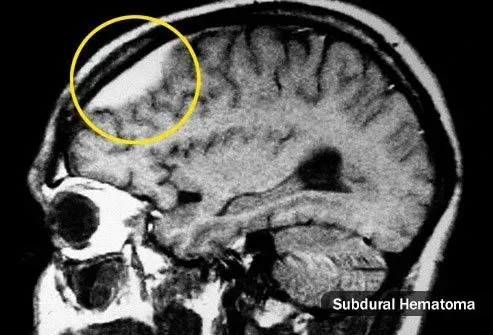

Удряхте главата си

Главоболието може да започне веднага или месеци след контузия. Те може да са на мястото на удара или по целия ви череп и могат да се влошат, когато сте стресирани. Причината не винаги е ясна, но понякога твърде много кръв се натрупва на едно място. Това се нарича хематом. В сериозни случаи може да се почувствате слаби объркани гадни и забравителни. Вижте Вашия лекар, ако имате някой от тези симптоми или ако имате главоболие, след като ударите главата си.